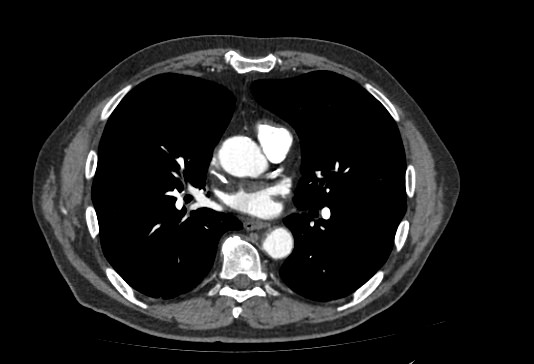

Компьютерная томография позволяет детально визуализировать структуру лимфатических узлов, выявить ее неоднородность, гиперплазию, определить деформацию контуров, появление инфильтрации окружающих тканей с образованием пакетов и конгломератов лимфоузлов.

В нашей клинике обследование лимфоузлов брюшной полости и забрюшинного пространства выполняется на современном мультиспиральном томографе экспертного класса TOSHIBA AQUILION CXL, который при помощи рентгеновских лучей производит послойное сканирование исследуемой области. Аппарат оснащен 128 высокочувствительными детекторами, расположенными по спирали, что позволяет за короткое время выполнять сканирование нескольких областей тела. Это значительно сокращает время исследования и снижает уровень лучевой нагрузки на пациента.

Полученные данные посредством инновационных цифровых приложений преобразуются в трехмерные изображения высочайшего качества, что позволяет проводить точную и достоверную диагностику.

С целью повышения контрастности изображений, выявления патологических изменений в лимфоузлах дополнительно внутривенно вводится рентгеноконтрастное вещество на основе йода. Контраст накапливается в патологических очагах и под воздействием рентгеновских лучей обусловливает их яркое изображение на фоне неизмененной ткани. Контрастирование значительно повышает диагностическую ценность исследования и помогает выявлять многие серьезные заболевания на начальных этапах.